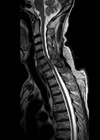

Case 1 1. What does this sagittal magnetic resonance imaging (MRI) scan show? 2. Which cancers commonly cause this? 3. What is the acute management? Case 2 1. What is the diagnosis? 2. What local effects can this mass cause?...